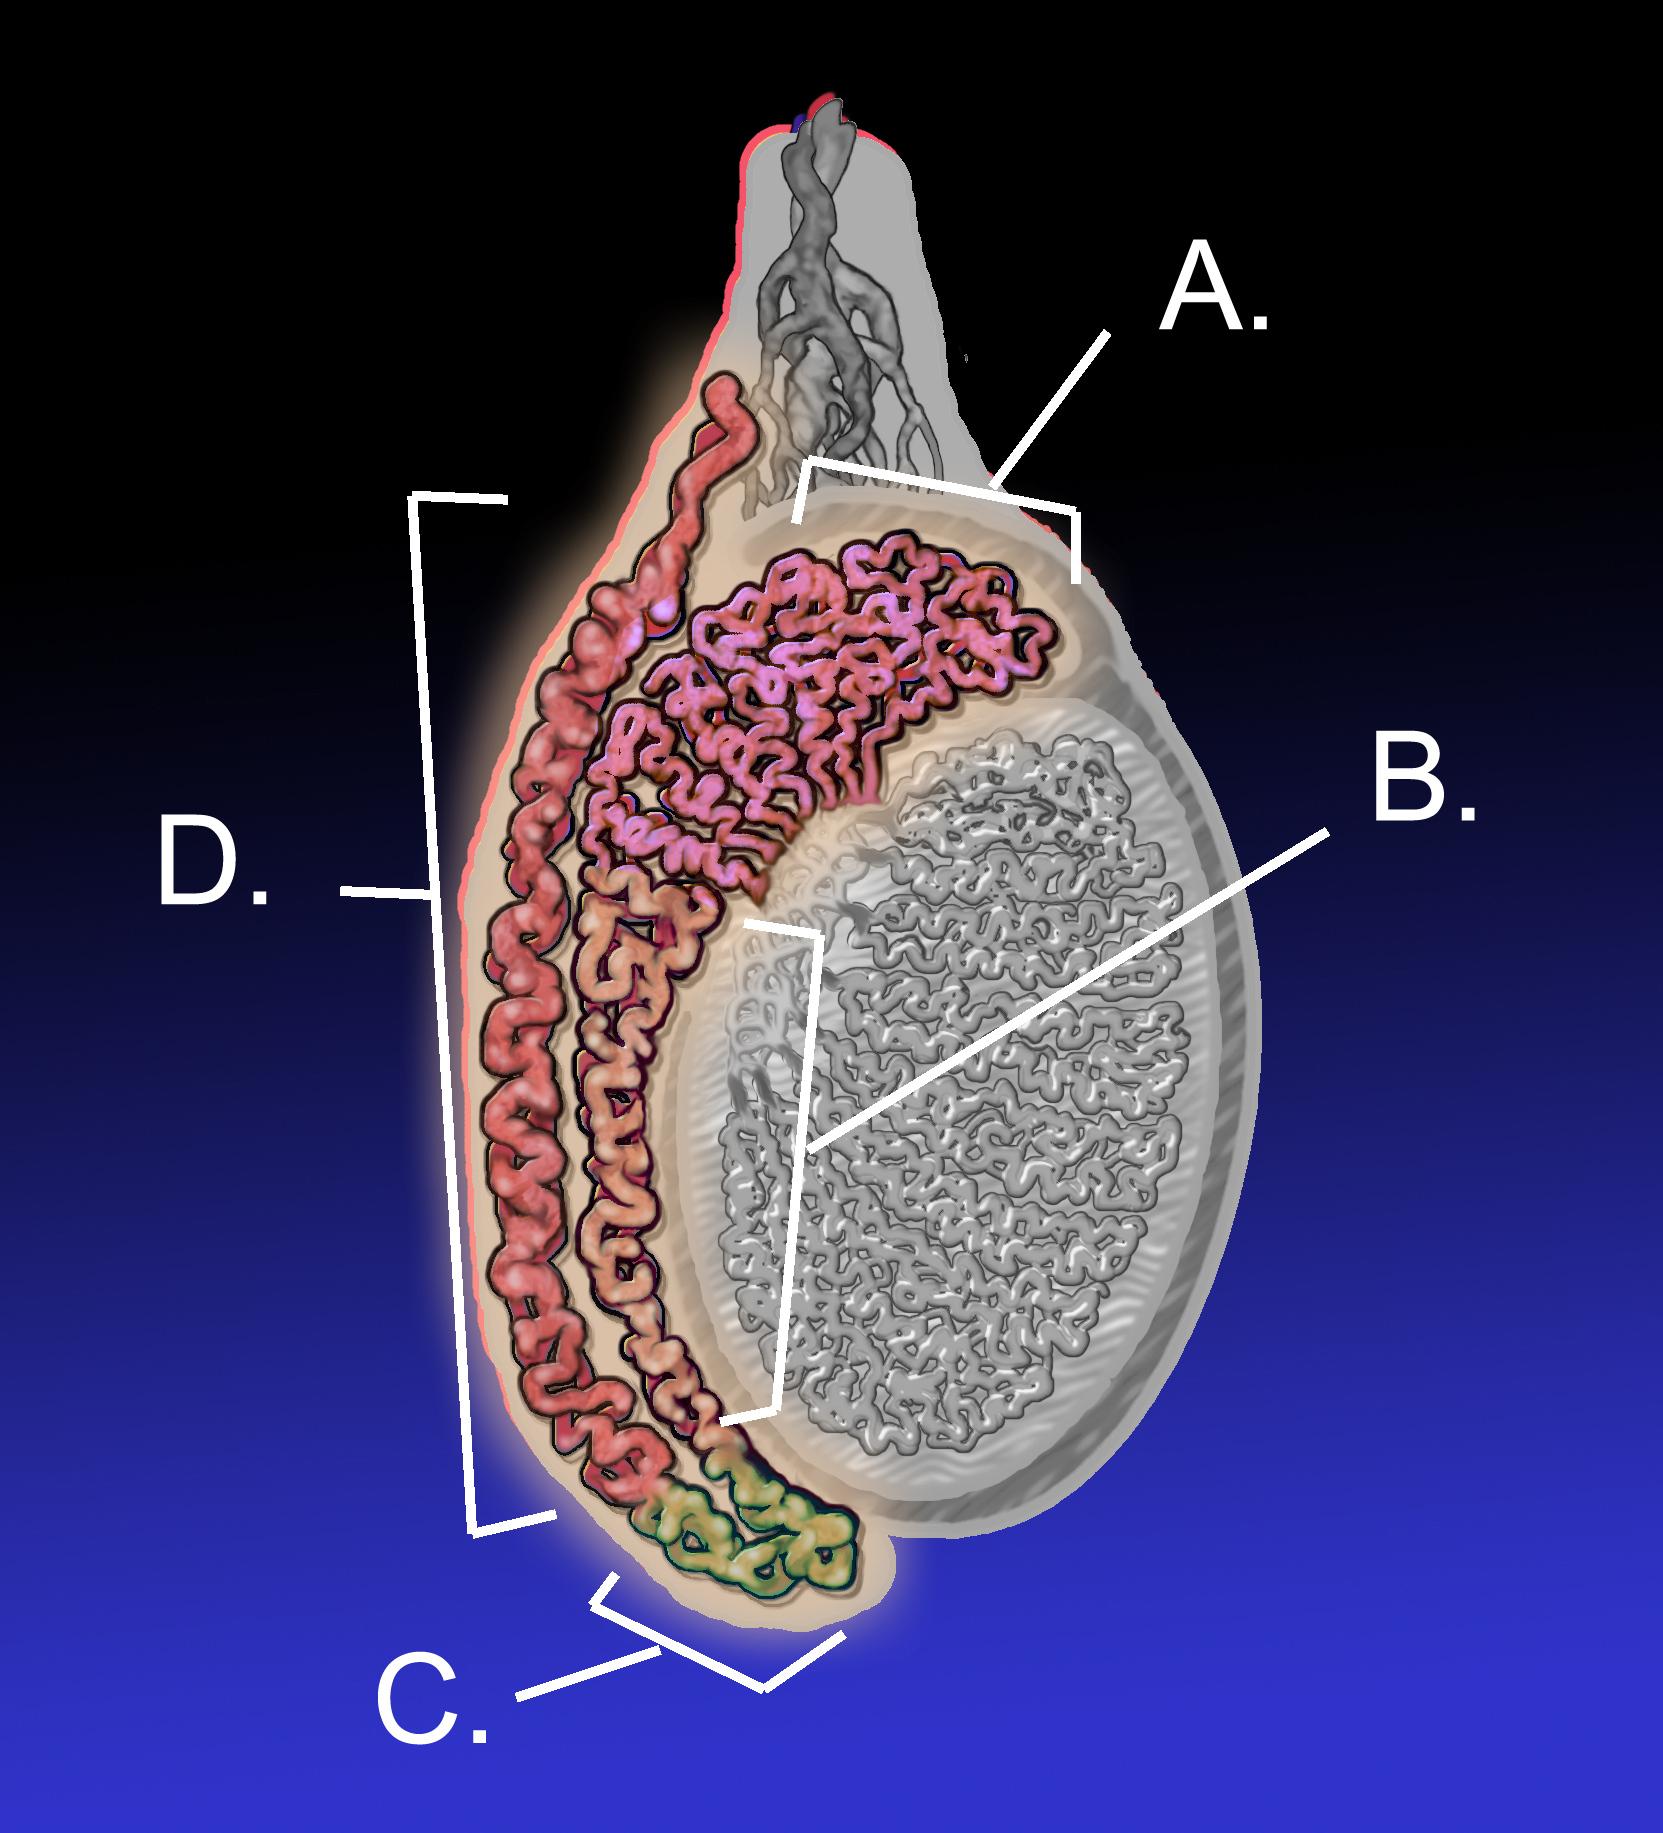

부고환염은 부고환의 염증으로, 주로 16세에서 30세 사이의 남성에게서 발생한다. 급성 부고환염의 가장 흔한 원인은 세균 감염이며, 성적으로 활동적인 남성의 경우 클라미디아 트라코마티스가 주요 원인이다. 비감염성 원인으로는 무균 뇨의 역류, 소아의 바이러스 감염, 사르코이드증 등이 있다. 증상으로는 음낭의 통증과 부종, 발열 등이 나타나며, 고환 염전과 감별이 필요하다. 진단은 증상과 도플러 초음파 검사를 통해 이루어지며, 치료는 항생제 투여가 일반적이다. 합병증으로는 농양, 불임, 만성 통증 등이 있을 수 있다.

급성 부고환염은 며칠에 걸쳐 발생하며 통증, 부종이 한쪽 고환에서 나타나고 고환이 아래로 처진다. 배뇨 곤란, 요도 분비물, 발열이 나타날 수 있다.[4] 만성 부고환염의 경우, 환자는 통증이 있는 압통을 느낄 수 있지만, 촉진 시 부고환이 불규칙하거나 경화된 부고환이 나타날 수 있다. 음낭 초음파 검사로 확인할 수 있지만, 특이 소견이 없는 경우도 있다. 만성 부고환염으로 진단받는 환자의 대다수는 5년 이상 증상을 겪었다.[13]

부고환염 진단은 주로 증상을 통해 이루어진다.[1] 음낭이 붉어지고, 따뜻하며, 부어오르는 증상과 함께 고환 뒤쪽에 통증이 느껴지는 것이 일반적이다. 고환거근 반사는 정상적으로 나타나는데, 이는 고환 염전과 구별하는 데 도움이 된다. 고환을 들어 올릴 때 통증이 줄어드는 프렌 징후는 진단에 큰 의미가 없다.[9]

진단은 일반적으로 증상을 기반으로 한다.[1] 유사한 증상을 유발할 수 있는 질환으로는 고환 염전, 서혜부 탈장, 고환암 등이 있다.[1] 진단이 불분명한 경우 도플러 초음파 검사가 유용할 수 있다.[1]

부고환염은 일반적으로 서서히 시작된다. 전형적인 소견으로는 음낭의 발적, 온열감 및 부종이 있으며, 고환 뒤쪽, 즉 중앙에서 떨어진 부위에 압통이 있다(이것이 고환에 대한 부고환의 정상적인 위치이다). 고환거근 반사(허벅지 안쪽 위를 쓸어 올렸을 때 고환이 올라가는 현상)는 정상적으로 유지된다.[1] 이는 고환 염전과 구별하는 데 유용한 징후이다. 고환을 들어 올렸을 때 통증이 완화되면 이를 프렌 징후라고 하는데, 이는 특이성이 없어 진단에 유용하지 않다.[9]

정교한 의학 영상 기술이 개발되기 전에는 외과적 탐사가 표준 치료법이었다. 오늘날에는 도플러 초음파 검사가 일반적인 검사이다. 이는 혈류 영역을 보여주고 부고환염과 염전을 명확하게 구별할 수 있다. 그러나 염전 및 고환 통증의 다른 원인은 촉진만으로도 종종 확인할 수 있으므로, 일부 연구에서는 초음파의 유일한 실질적인 이점은 고환암이 없음을 환자에게 확신시키는 것이라고 제안했다.[10] 핵의학적 고환 혈류 검사는 드물게 사용된다.

정교한 의학 영상 기술이 개발되기 전에는 외과적 탐사가 표준 치료법이었다. 오늘날에는 도플러 초음파 검사가 일반적인 검사이다.[10] 이는 혈류 영역을 보여주고 부고환염과 염전을 명확하게 구별할 수 있다. 그러나 염전 및 고환 통증의 다른 원인은 촉진만으로도 종종 확인할 수 있으므로, 일부 연구에서는 초음파의 유일한 실질적인 이점은 고환암이 없음을 환자에게 확신시키는 것이라고 제안했다.[10] 핵의학적 고환 혈류 검사는 드물게 사용된다.